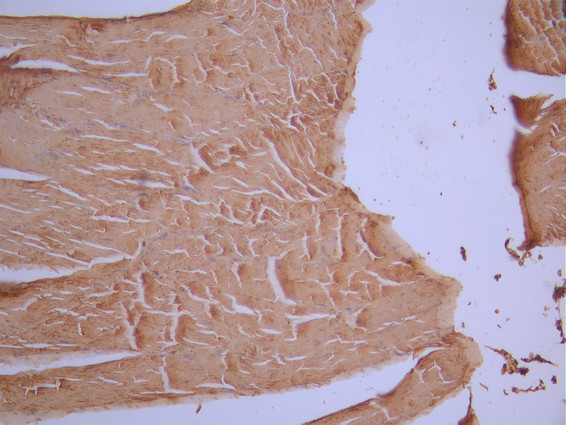

IHC image of CSB-RA008424MA2HU diluted at 1:50 and staining in paraffin-embedded human skeletal muscle tissue performed on a Leica BondTM system. After dewaxing and hydration, antigen retrieval was mediated by high pressure in a citrate buffer (pH 6.0). Section was blocked with 10% normal goat serum 30min at RT. Then primary antibody (1% BSA) was incubated at 4°C overnight. The primary is detected by a Anti-Human lgG, Fcy Fragment Specific labeled by HRP and visualized using 0.05% DAB.